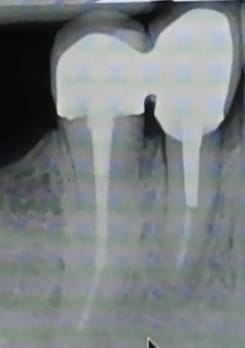

Cas ultra classique mais j'aimerais en discuter avec vous.

Ma voisine de 40 ans, adorable, en bonne santé qui a fait une pulpite sur 14 cet été ; le dentiste en urgence lui a mis un pansement pour la soulager.

J'ai fait l'endo, la préparation pour IC bientôt je ferai l'élongation coronaire en distal mais je trouve que tout cela est terriblement "mutilant"

la 14 a une ligne de faiblesse (sillon O MD, ligne de coalescence des bourgeons lors de la formation), pour moi la dent qui se fracture le plus (vu plusieurs fois même sur dent saine et dragée ou bonbon dur) et alors c'est toujours soit l'éclatement total d'emblée soit la fracture en biseau bien sous gingival.

Moi aussi je ferais une coiffe. Par contre pour l'INCO , j'en suis revenue,( cf les considerations d'Enlaye sur les INCO), ici en particulier des racines toujours plus grêles que ce qu'on aurait imaginé, des accumulations de contraintes mal réparties sur les parois, un bras de levier(partie intra osseuse/ suparo osseuse) rendu plus defavorable du fait de la nécessité d'élongation coronaire.... une meilleure "diffusion " si reconstitution compo... donc de préference si possible.

je rajoute l'onlay ne protégera pas d'un effet de coin, ce que je redoute sur cette dent là en particulier (sa morpho).

Difficile de se rendre compte sur la rétro du degré de délabrement.

L ' IC est il vraiment nécessaire ? l' élongation coronaire est elle vraiment nécessaire?

J' aurais fait également une couronne avec une préparation verticale pour être le plus conservateur possible.

Pourquoi une élongation coronaire? Tu peux faire une limite sous gingivale juxta (je dirais même légèrement supra vu la radio, mais sans certitude) osseuse.

Le reste comme les autres, selon le délabrement, soit onlay, soit RCR +couronne.